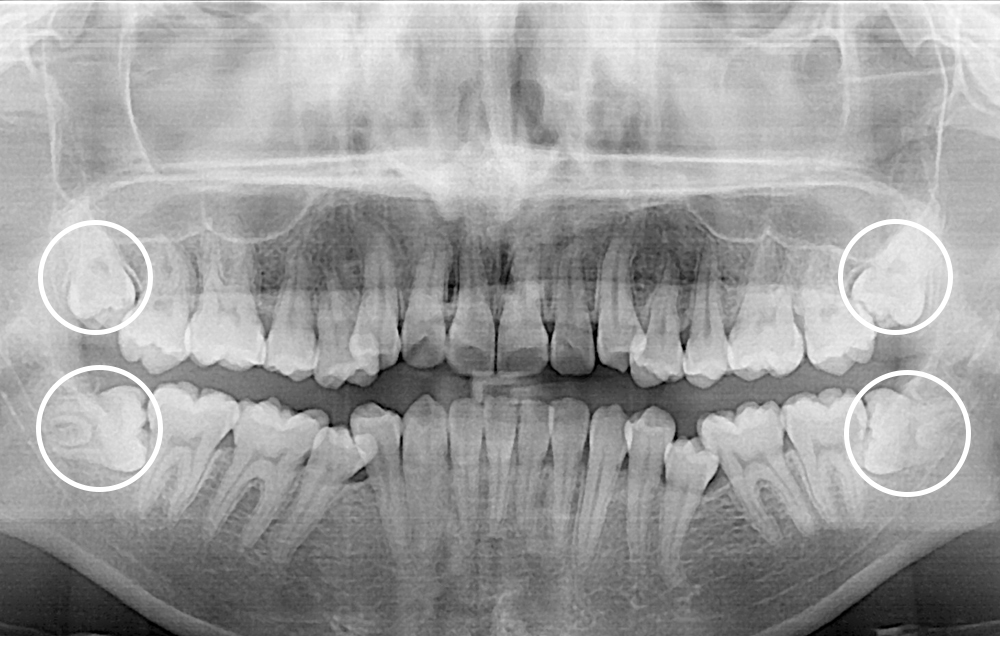

[사랑니] 매복 사랑니 발치

치료후 : 2020-06-23

세종치과는 구강악안면외과학 박사이신 원장님이 발치하는 치과입니다.